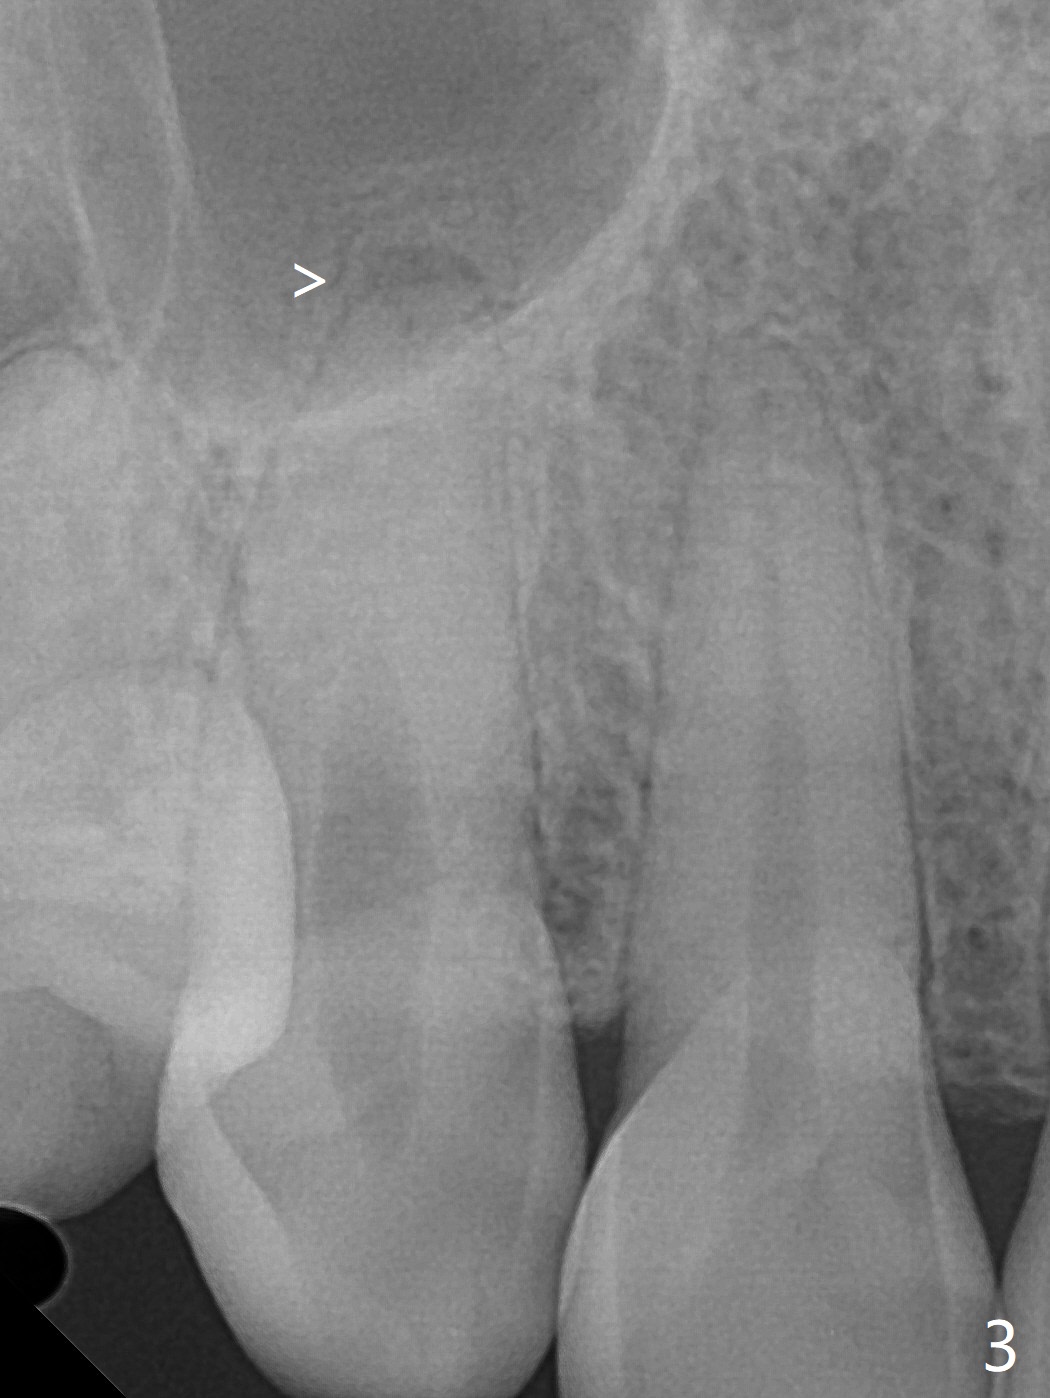

A 36-year-old woman (after #3 immediate implant and #31 socket preservation) wants to take care of the discolored canine 20 years post orthodontic treatment with extraction (Fig.1-3). RCT (Fig.4) appears to whiten the tooth (Fig.5 (A4)). The darkness appears to rebound 1 month post RCT, after removal of Gutta Percha for take home internal and external bleaching (Fig.6). The patient returns for composite after 3-week whitening (Fig.7,8). The shades of composite are bleach (flowable, C1) and B1 (packable, C2, Fig.9). The shade of the RCT tooth is compatible with that of the neighboring teeth 4 months post composite (Fig.10) when the implant at #3 has a new abutment.